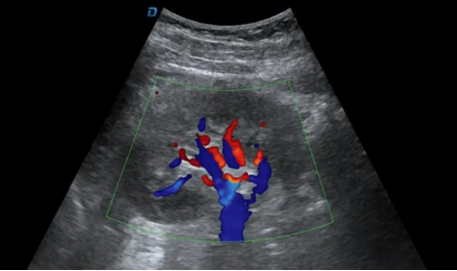

彩超是在黑白超图像的基础上,叠加了“彩色多普勒”技术。这项技术利用超声波探测血液流动的方向和速度,并用红色和蓝色进行编码:通常,红色代表血流朝向探头方向流动,蓝色则代表血流远离探头。这样一来,医生就能直观地看到血管分布、血流是否通畅、有无异常狭窄或反流等情况。

需要特别注意的是,在彩超检查中,只有当医生启动血流检测模式时,屏幕上才会出现彩色的血管信号;而在观察器官结构时,图像仍以黑白色为主。所以,如果检查时大部分画面是黑白的,并不代表仪器“不是彩超”,而是因为当前正在评估的是组织结构,而非血流状态。